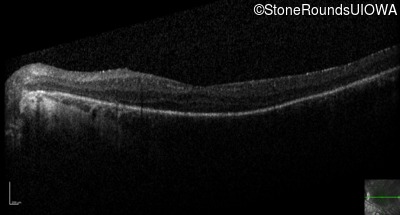

Optical Coherence Tomography - Right - 20/40

Exemplar / OCT Stack